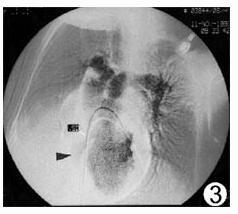

三尖瓣閉鎖三尖瓣閉鎖是一種紫紺型先天性心臟病,發病率約占先天性心臟病的1~5%。在紫紺型先天性心臟病中繼法樂四聯症和大動脈錯位後居第三位。主要病理改變是三尖瓣閉鎖或三尖瓣口缺失,卵圓孔未閉或房間隔缺損。詳細見三尖瓣閉鎖。

三尖瓣關閉不全

罕見於瓣葉本身受累,而多由肺動脈高壓及三尖瓣擴張引起。由於先天性或後天性因素致三尖瓣病變或三尖瓣環擴張,導致三尖瓣在收縮期不能完全關閉時稱三尖瓣關閉不全。該病有功能性和器質性兩種,前者多繼發於導致右心室擴張的病變,發病率相當高,如原發性肺動脈高壓、二尖瓣病變、肺動脈瓣或漏斗部狹窄、右心室心肌梗塞等。後者可為先天性異常如Ebstein畸形及共同房室通道,也可為後天性病變如風濕性炎症、冠狀動脈病變致三尖瓣乳頭肌功能不全、外傷及感染性心內膜炎等。該病預後視原發病因的性質和心力衰竭的嚴重度而定,原發性肺動脈高壓症和慢性肺源性心臟病所致者預後常較二尖瓣病變或房間隔缺損所致者更差。內科治療可緩解症狀,外科手術可治癒。詳細見三尖瓣關閉不全。

三尖瓣下移畸形是一種罕見的先天性心臟畸形。1866年Ebstein首先報導一例,故亦稱為Ebstein畸形。其發病率在先天性心臟病中占0.5~1%。三尖瓣下移畸形系指三尖瓣畸形,其後瓣及隔瓣位置低於正常,不在房室環水平而下移至右心室壁近心尖處,其前瓣位置正常,致使右心房較正常大,而右心室較正常小,可有三尖瓣關閉不全。此類畸形常合併卵圓孔開放或房間隔缺損以及肺動脈狹窄。由於右心房內血量較多,壓力增高,其所含血液部分經房間隔缺損或卵圓孔流入左心房,部分仍經三尖瓣入右心室,因肺動脈狹窄,進入肺循環的血量減少,故回入左心房的動脈血量也少,此時再與自右心房分流來的靜脈血混合,經二尖瓣而入左心室及體循環。詳細見三尖瓣下移畸形。